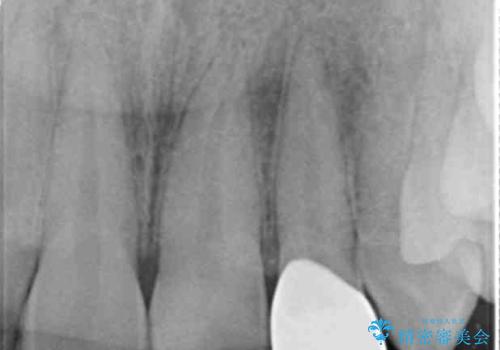

- 他院で昨年治療したセラミッククラウンが欠け、審美性の改善を求めて来院されました。

噛み合わせからクラウンが欠けやすい状態だったので、欠けにくく強度に優れるフルジルコニアクラウンで審美性を改善します。

フルジルコニアクラウンは若干透明感に劣る反面、強度に優れ大きな力のかかる部位に有効な補綴方法です。